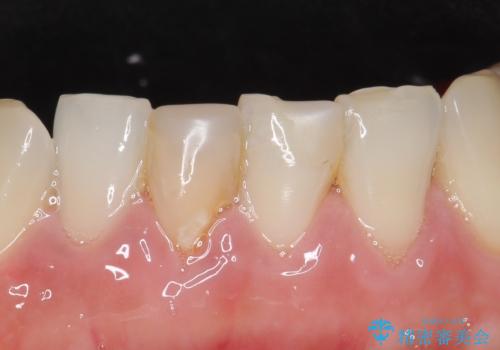

- 下顎前歯の見た目が気になるといらっしゃった方の症例です。

右下1の再根管治療終了後、オールセラミッククラウン(スペシャル)による補綴を行いました。

前歯の補綴ではオールセラミッククラウンを希望される患者様が多いですが、オールセラミッククラウンの中でも、エコノミー、スタンダード、スペシャル、エクセレントとランクがあります。

その中でも特に審美性が高いのがスペシャル、エクセレントです。スペシャル、エクセレントは口腔内写真をもとに熟練の技工士が、患者様の口腔内に合わせたオーダーメイドのクラウンを製作致します。